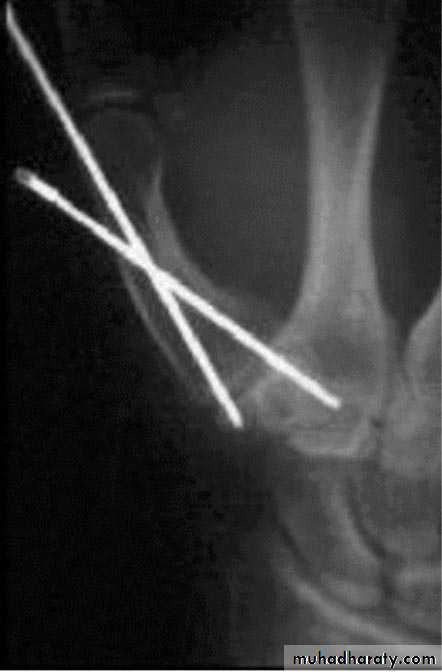

Displaced fracture: open reduction and internal fixation.

Surgical treatment